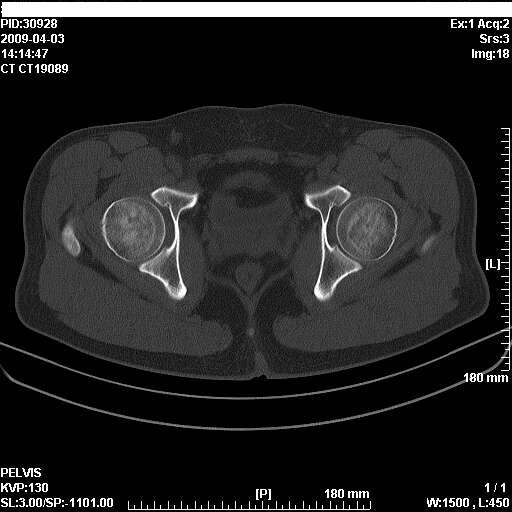

以下是引用随光逐影在2009-4-4 15:13:00的发言:[br]考虑双侧股骨头无菌性坏死;建议行mri检查进一步明确诊断。

以下是引用余辉在2009-4-4 14:22:00的发言:[br]双侧髋关节诸构成骨未见明显异常.必要时mr检查[br]患者症状已有两年,可能要同时从其他方面找原因,个人觉得不排除双侧骶髂关节有问题,建议ct检查